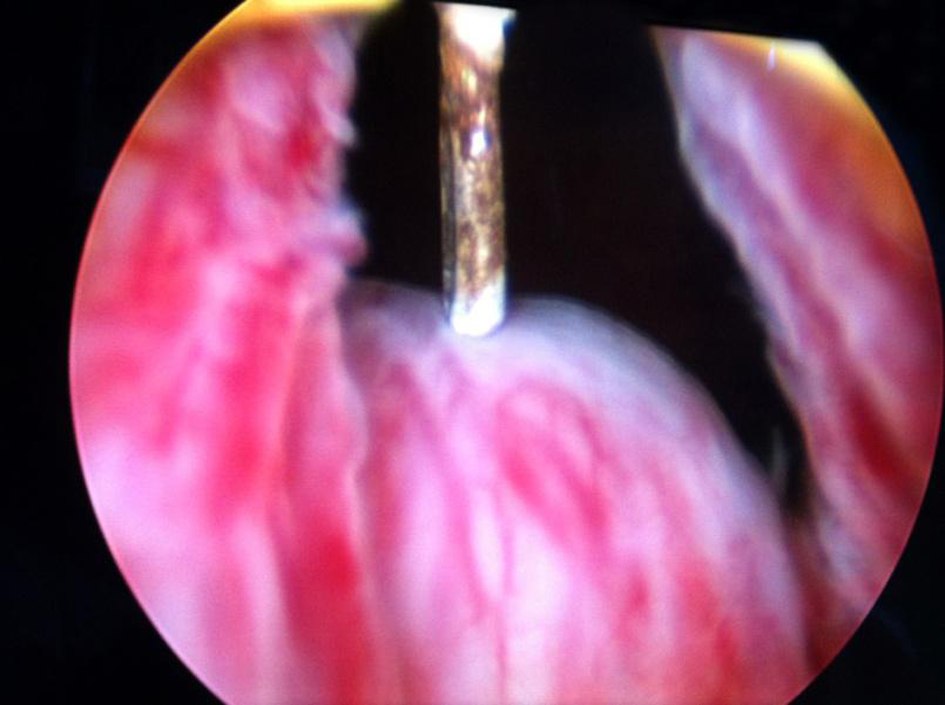

Cystourethroscopy revealed bilateral ectopic ureters opening into prostatic urethra just proximal to the verumontanum. Left ureteric opening was patulous (Fig. 4). Right ureterocele was visible in the empty bladder with a dimple of stenosed opening and this ureterocele was overlapping and obstructing the left ureteric opening (Fig. 5). Right ureterocele got effaced on distending the bladder and bladder neck was wide open. Trigone was absent. Urinary bladder was of normal capacity, congested and mildly trabeculated. Ureteroscope when passed into left patulous ureteric opening led to dilated tortuous left ureter. Right ureteric opening could not be identified.

![]() Click for large image | Figure 4. Left patulous ureteric opening with effaced right ureterocele. |